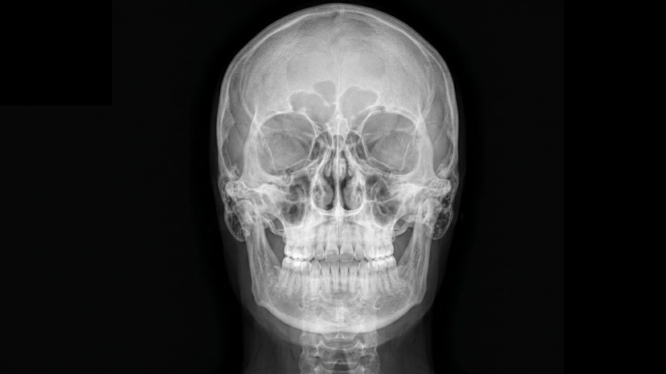

📸 ¿Qué es una radiografía anteroposterior dental?

La radiografía anteroposterior (AP) es un estudio radiográfico en el que:

➡️ El haz de rayos X entra por la parte frontal del rostro

➡️ Y atraviesa las estructuras hacia la parte posterior

Esto permite obtener una imagen frontal del cráneo y estructuras dentofaciales, ideal para evaluar:

✔️ Simetría facial

✔️ Estructuras óseas

✔️ Relación entre maxilar y mandíbula

✔️ Posición de dientes incluidos o impactados

💡 En términos simples:

Es como ver el rostro “desde dentro”, de frente, con una precisión imposible de lograr solo con exploración clínica.